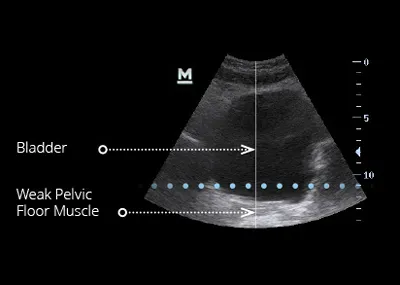

EMsella is a non-invasive treatment that uses high-intensity focused electromagnetic (HIFEM) technology to strengthen the pelvic floor muscles and improve bladder control. While you sit fully clothed on the EMsella chair, the technology delivers thousands of deep pelvic floor contractions—the equivalent of doing 11,000 Kegel exercises in just one 28-minute session.

The Emsella chair uses the same trusted HIFEM technology found in EMsculpt NEO. As you sit fully clothed, electromagnetic energy penetrates deeply into the pelvic floor area, inducing supramaximal pelvic-floor muscle contractions that would be impossible to perform voluntarily. These contractions re-train weak muscles, improve bladder control, and restore confidence.

In a single 28-minute session, the treatment delivers the equivalent of over 11,000 Kegel exercises, which are extremely important in muscle re-education, restoring neuromuscular control and improvement of intimate wellbeing.